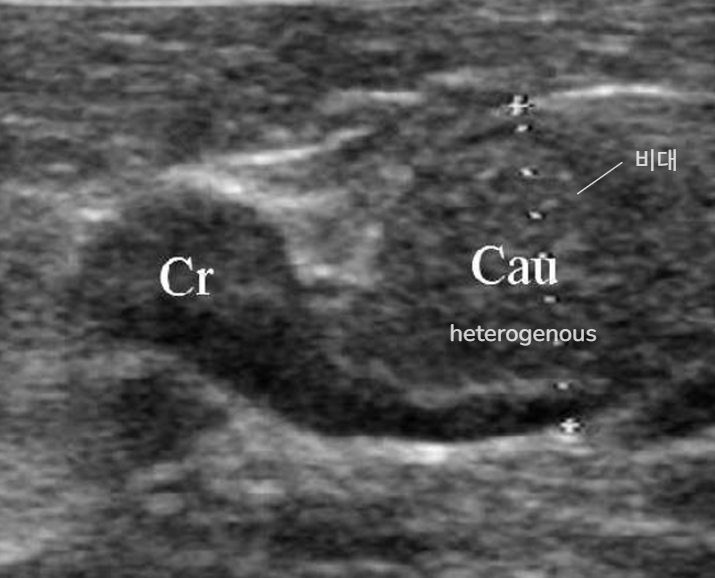

| - ํธ์ธก ๋น๋ - ์ข ์ํ๋ ์กฐ์ง์ ์ํฅ์ ์ ๋ฐ๊ณ - ๋ฐ๋์ชฝ ์กฐ์ง์ ์์ถ (์ด๋ฏธ ๊ณผ๋ํ ๋ถ๋น) - ๊ฐ์๊ธฐ ์ ์ ํด๋ฒ๋ฆฌ๋ฉด ์ ์ ๋ถ๊ฐ - ํ๋ณต ๋๊น์ง ์คํ ๋ก์ด๋ ํฌ์ฝ ํ์ | |

| U/S - ๋น๋ (Cr/Cd ํ์ชฝ๋ง ๋น๋๋ผ๋ O) | ![]() |